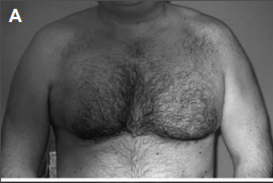

Paciente varón de 36 años, levantador de pesas amateur, que acudió a consulta

refiriendo deformidad de la cara anterior del hombro y pérdida de fuerza en rotación interna y aducción de hombro derecho de dos meses de evolución. El cuadro clínico se inició al escuchar un crujido y dolor intenso en la región anterior del hombro derecho al iniciar el levantamiento de una barra horizontal de pesas en antepulsión desde la posición de decúbito supino.

¿Qué músculo es el principal aductor, rotador interno y anteversor del brazo?

RESPUESTA CORRECTA: Opción 3

- Pectoral mayor (Opción 3: CORRECTA): es el único músculo del miembro superior que hace aducción, rotación interna y anteversión de manera principal.